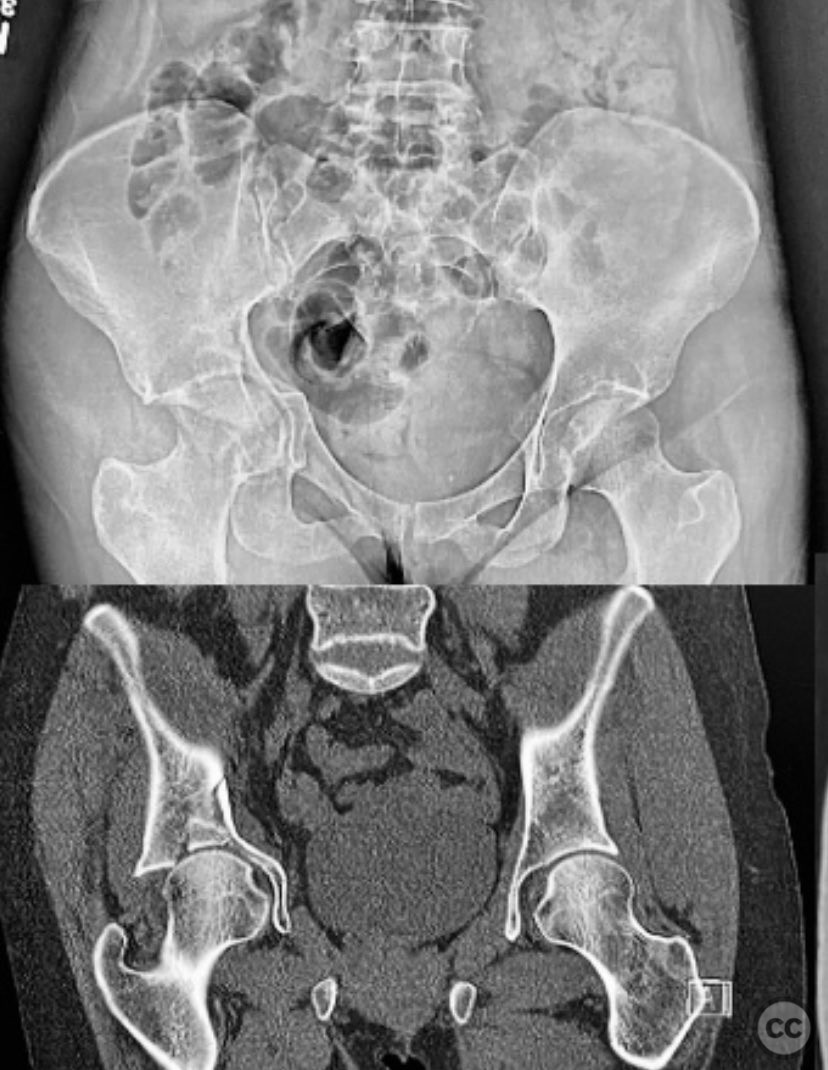

Acetabulum - AO/OTA 62x